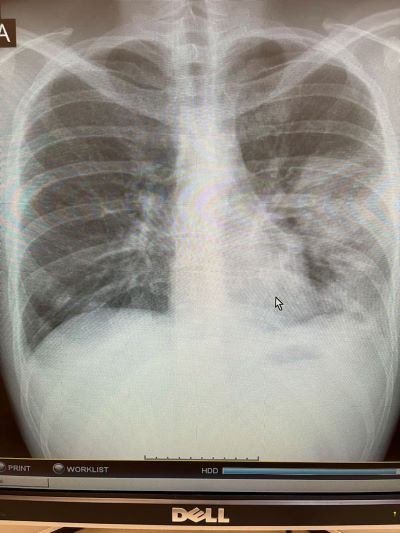

Рентгеновские снимки при пневмоцистной пневмонии